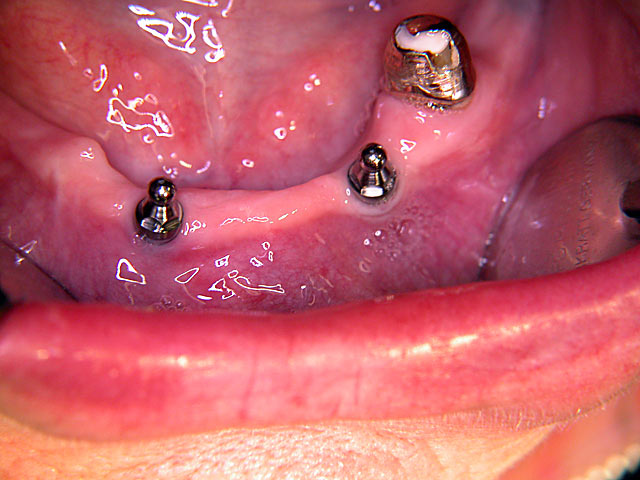

Kurzimplantate und Sofort – Implantate: